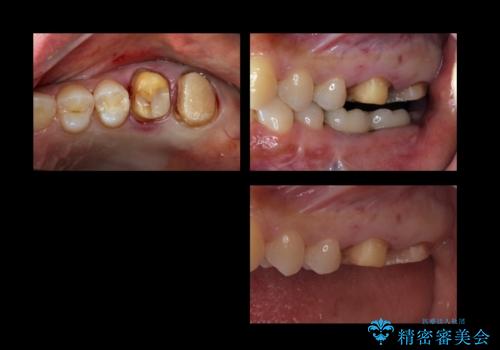

下の奥歯が虫歯になっており、痛みが生じていました。

左右の第二大臼歯は虫歯がひどく抜歯が必要な状態でした。

また、左下の第一大臼歯は歯が内側から吸収してしまう状態(外部吸収)が生じており、患者様と相談の上抜歯しました。